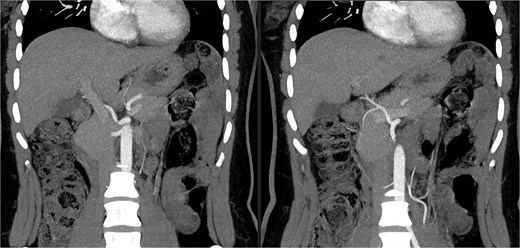

A 27-year-old woman, with no notable medical history, was evaluated as a living donor for her 9-year-old son with hepatic failure. The preoperative workup included an abdominal-pelvic CT angiogram and a biliary MRI. The biliary MRI showed normal biliary ducts. However, the CT angiogram revealed a significant vascular variation: the absence of the typical celiac trifurcation (Figs 1 and 2). The celiac trunk gave rise only to the left gastric artery and the splenic artery, forming a gastrosplenic trunk, while a second arterial trunk originating from the abdominal aorta at the level of L1 simultaneously gave rise to the SMA and the CHA: a hepatomesenteric trunk.

3D reconstruction using Myrian software illustrating the arterial anatomical variation.